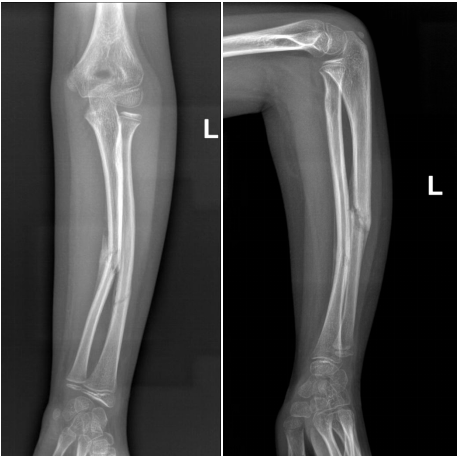

7岁的黎同学,上学时不慎摔倒导致左前臂疼痛畸形。当地医院X片提示“左侧尺桡骨干骨折”。

术前骨折断端移位明显